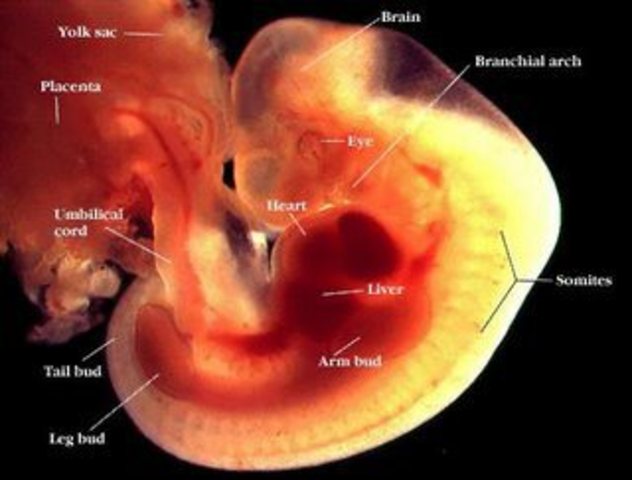

• Week Six

Week Six

•The embryo has reached a size of about 8 mm (1/4 inch) in length.

•The spinal cord, which until now has been open, is beginning to close.

•The first blood cells and blood vessels are developing.

•Blood moves through these primitive vessels connected to the yolk sac.

•A pipe-shaped heart is formed and begins to beat.

•The brain begins to divide into 5 parts.

•Optic pits form the start of the developing eye.

•The cells destined to be the arms and legs are in place.

• Week 7

Week 7

•The embryo is around 13 mm (1/2 inch) in length.

•The heart is beating with one chamber.

•A dividing wall is formed in the heart.

•Arm and leg buds begin to grow.

•The lower jaw and the vocal cords are beginning to form.

•The mouth opening is formed.

•The inner ear is being created.

•The digestive tract is developing

•The navel string is being created

•The following organs are being formed: the lungs, the liver, the pancreas and the thyroid gland.